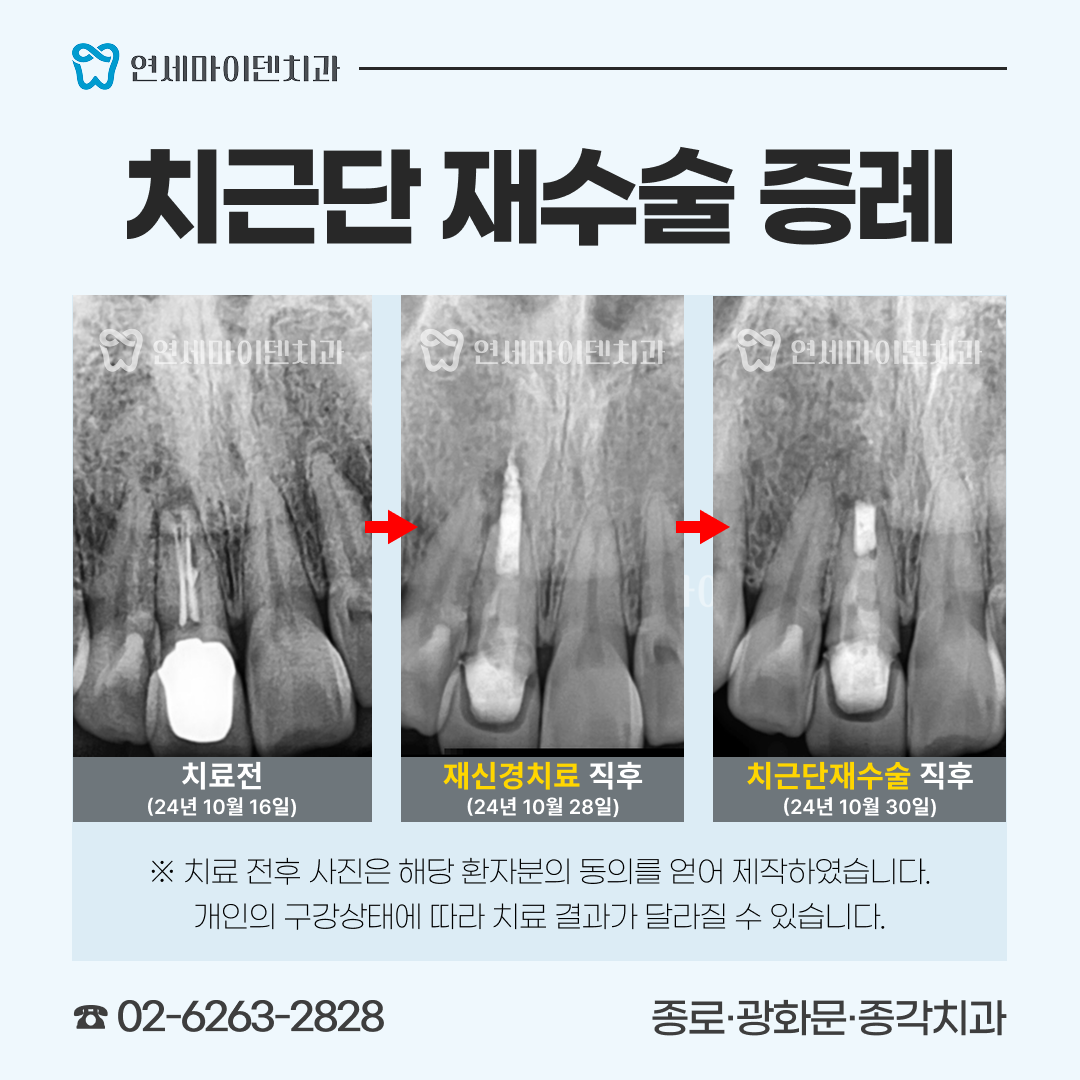

■ 환자의 주요 증상과 진단 과정

이 환자분은 '예전에 신경치료를 받았던 왼쪽 위 어금니쪽이 시린 증상이 있고 아프다'며 내원하셨는데요.

두 개의 치아 모두 불편함이 있었고, 모두 치료를 받은 지 꽤 되었으며, 염증이 있는 상태였습니다.

■ #25번, 첫 번째 치아 치료 - 재신경치료

살펴보니 과거에 받으셨던 신경치료의 퀄리티가 아쉬운 부분이 있었습니다.

신경관뿌리까지 치료가 되어있지 않고, 중간에 갭이 보였습니다.

치료를 조금만 하면 개선의 여지가 있겠다는 생각이 들어, 우선은 재신경치료를 하기로 했습니다.

거타퍼차 콘(GP cone)을 하나씩 꽂는 방식이 아닌, 수직 가압 충전법을 사용하여 거타퍼차 콘을 녹여 충전하는 현대적 방식으로 진행하였습니다. 레진 충전시에도 임시 재료 없이 원칙적인 치료로 진행했습니다.